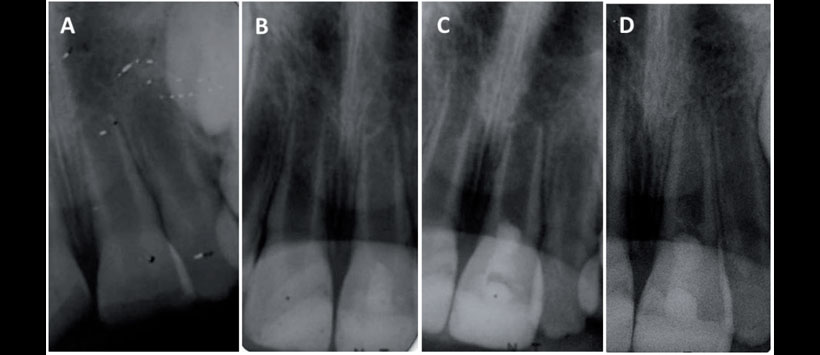

Los dientes permanentes jóvenes sin pulpa vital a menudo tienen paredes delgadas y frágiles, por lo que es difícil lograr la instrumentación eficiente y obtener el sellado apical adecuado. Adicionalmente, las paredes delgadas del conducto radicular pueden predisponer estos dientes a fracturas. (Figura 1)

Las opciones de tratamiento tradicionales incluyen apexificación con la utilización de medicación intraconducto (MIC) de hidróxido de calcio [Ca(OH)2 ], o la colocación del agregado de trióxido mineral (MTA) o Biodentine (Septodont, Saint-Maur-desFossés, Francia) como barrera apical antes de obturar el sistema de conductos radiculares.

Sin embargo, estas opciones de tratamiento requieren un pronóstico a largo plazo debido a las paredes de dentina delgadas, ápice no formado completamente y, en algunos casos, raíces cortas. Evaluar la posibilidad de extracción dental y sustitución por implante o prótesis fi ja está descartada debido a la etapa de dentición mixta y el continuo desarrollo cráneo-esquelético.